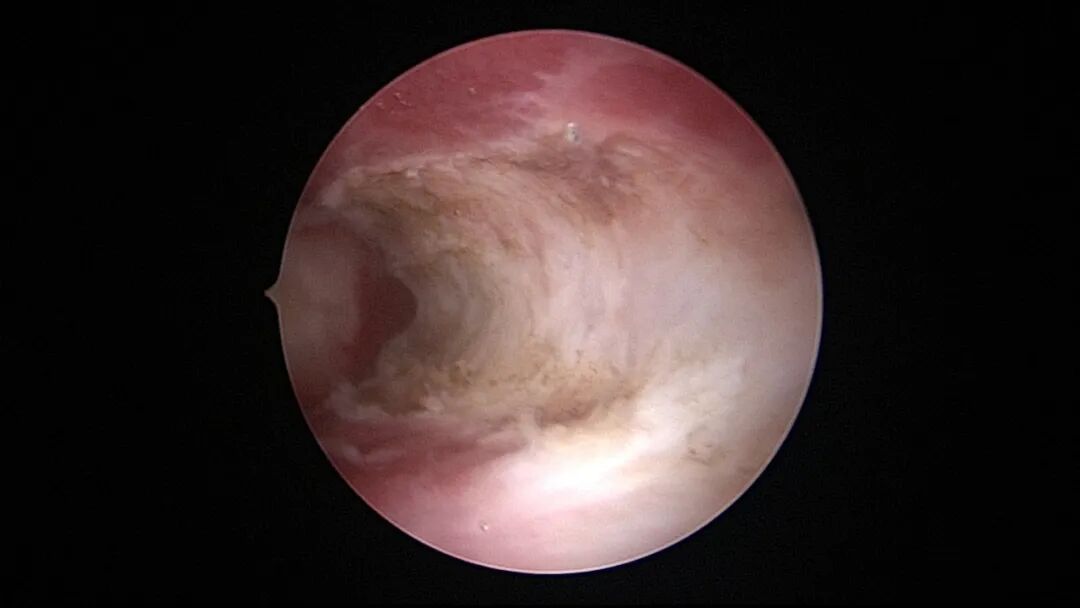

第一次宫腔镜:2021年4月,闭经50+天,B超提示宫腔粘连,宫腔镜探查见宫颈管上段封闭粘连,宫腔广泛粘连,AFS评12分(最高分)。宫腔镜单极电切分粘,恢复宫腔形态,显露双侧输卵管开口,右侧宫角附近内膜柔软、红润,宫腔防粘连复发处理。